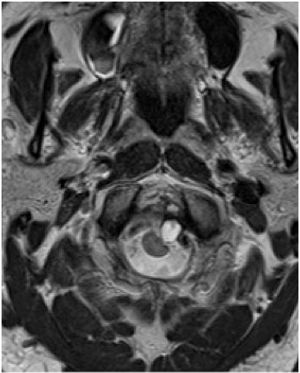

69-year-old man presents with headache.